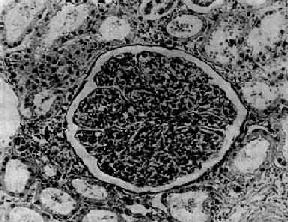

肾小球由毛细血管丛和肾球囊构成,是血浆滤过的器官。肾小球毛细血管壁分3层,中间为基底膜,内侧有内皮细胞覆盖,外侧为脏层上皮细胞。毛细血管基底膜厚约320nm,可分为三层,中间为致密层,内侧和外侧各为内疏松层和外疏松层。毛细血管基底膜内面由一层扁平的内皮细胞覆盖。内皮细胞胞浆很薄,布满许多直径约70~100nm的小孔。脏层上皮细胞(又称足细胞)在基底膜外侧,胞浆丰富形成许多细长的分枝状突起称为足突。上皮细胞由这些足突附着于基底膜外疏松层。足突之间形成许多间隙,宽约20~30nm,称为滤过隙。距基底膜表面约60nm,在相邻的足突之间有一层薄膜称为滤过隙膜。毛细血管壁包括内皮细胞、基底膜、上皮细胞,共同组成肾小球的滤过膜(图12-1)。肾小球的滤过除与毛细血管的结构和滤过物质的分子大小有关外,并与基底膜的生物化学组成及其电荷有关。基底膜主要由Ⅳ型胶原和一些糖蛋白如层连蛋白(laminin)、纤维连接蛋白(fibronectin)和多聚阴离子多糖蛋白(polyanionic proteoglcans)等组成。其中尤其是硫酸类肝素多糖蛋白(heparan sulfate proteoglycan)带大量负电荷分布于内、外疏松层。此外,在毛细血管内皮细胞和脏层上皮细胞表面也有带负电荷的唾液酸糖蛋白(sialoglycoprotein)。肾小球的负电荷可阻止血液中带负电荷的分子如白蛋白滤过。当肾小球多聚阴离子减少时滤过的蛋白质可增加。

图12-1 正常肾小球滤过膜

Bm基底膜;En内皮细胞;Ep上皮细胞;L毛细血管腔;P上皮细胞足突;Rb红细胞短箭头为滤过隙;长箭头为滤过隙膜 ×14790